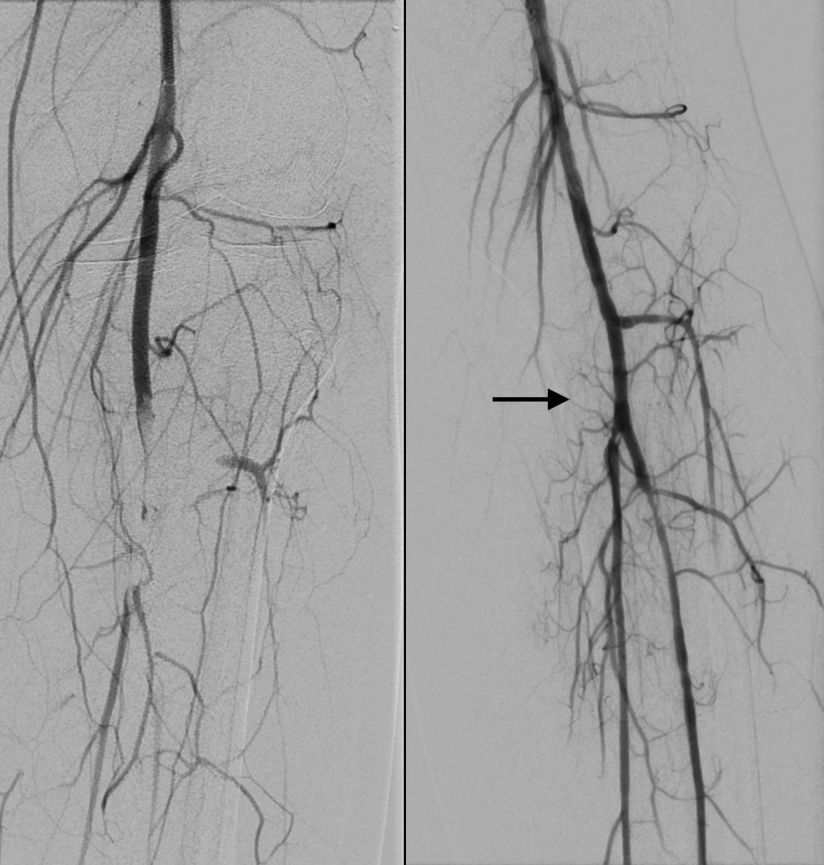

2、心血管造影是一种有创医学影像技术,通过向血管内注入造影剂并利用X射线成像,清晰显示心脏和血管的形态结构及功能,辅助诊断和治疗心血管疾病其核心原理是造影剂在X射线下显影,使血管结构可视化,具体检查项目及临床意义如下1 冠状动脉造影通过导管将造影剂注入冠状动脉,评估血管狭窄堵塞或畸形情。

6、心血管造影是通过向血管内注入造影剂,利用X线等影像学技术使心脏和血管显影,以清晰显示心血管形态结构和功能的检查方法一主要类型1冠状动脉造影检查冠状动脉是否存在粥样硬化狭窄或阻塞,是诊断冠心病的“金标准”2心脏造影评估心脏结构如心房心室大小形态及瓣膜功能,辅助诊断。

8、心血管造影是一种通过向血管内注入造影剂,利用X射线或其他成像设备显示心脏和血管形态结构及血流情况的影像学技术,用于诊断多种心血管疾病其原理基于造影剂在X射线下的对比效果将造影剂通过导管注入心脏或血管后,造影剂随血液流动,X射线拍摄可清晰显示心脏和血管的轮廓走行及病变情况,如狭窄。

10、心血管造影术是一种通过注入造影剂使心血管显影的诊断技术具体解释如下技术原理该技术是将含有机化合物在X线照射下透明的造影剂快速注入血流中,使心脏和大血管腔在X线照射下显影显影过程通过快速摄片电视摄影或磁带录像等方法,将心脏和大血管腔的显影过程拍摄下来从显影结果中,可以观察到含有造影剂的血液流动顺序以及心脏大。

16、心血管造影是心内科完成的一种微创检查手段以下是关于心血管造影的详细解释检查方式通过穿刺桡动脉或股动脉的方式,置入导引导丝和导管在冠状动脉血管的开口处注射造影剂显影原理在X线下,造影剂会在冠状动脉内显影通过不同方位的显影,可以清晰地观察到冠状动脉的形态和结构诊断作用判断有。